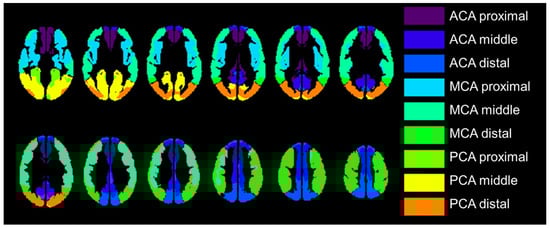

The transit time-based ROI value extraction was used in the comparison between PET and ASL parametric images, which were categorized into 18 regions: the left and right proximal, intermediate, and distal regions of each of the major anterior cerebral artery (ACA), middle cerebral artery (MCA), and the posterior cerebral artery (PCA) territories, which is previously reported and available in MNI standard space [26]. Figure 2 shows transit time-based ROIs. Relative CBF value in each ROI was calculated relative to the whole gray mask CBF value in each PET and ASL-CBF. We selected the MCA ROIs when we compared ROIs with affected and nonaffected cerebral flow based on the PET-CVR less than mean value of 30%.

Figure 2.

The regions of interest (ROI) were placed proximal, middle, and distal to the major vascular territories with structures located in the deep gray matter not included (e.g., basal ganglia and thalamus); 18 regions were measured per case. ACA, anterior cerebral artery; MCA, middle cerebral artery; PCA, posterior cerebral artery.